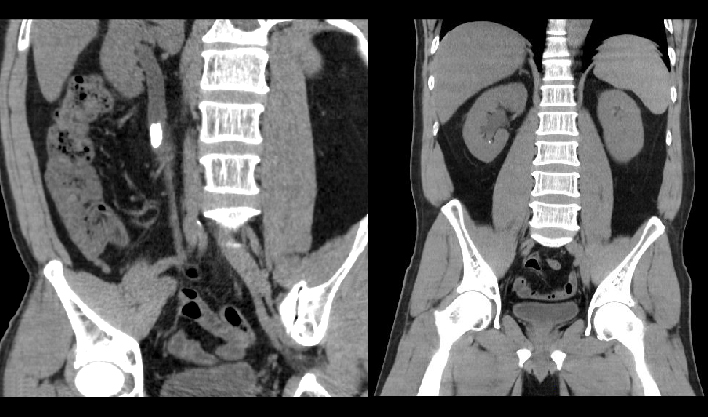

百万像素成像

1024x1024重建矩阵结合薄层成像,快速锁定微小病灶(如早期肿瘤、卒中病灶),助力急诊创伤、肿瘤筛查、卒中救治的“分秒必争"。